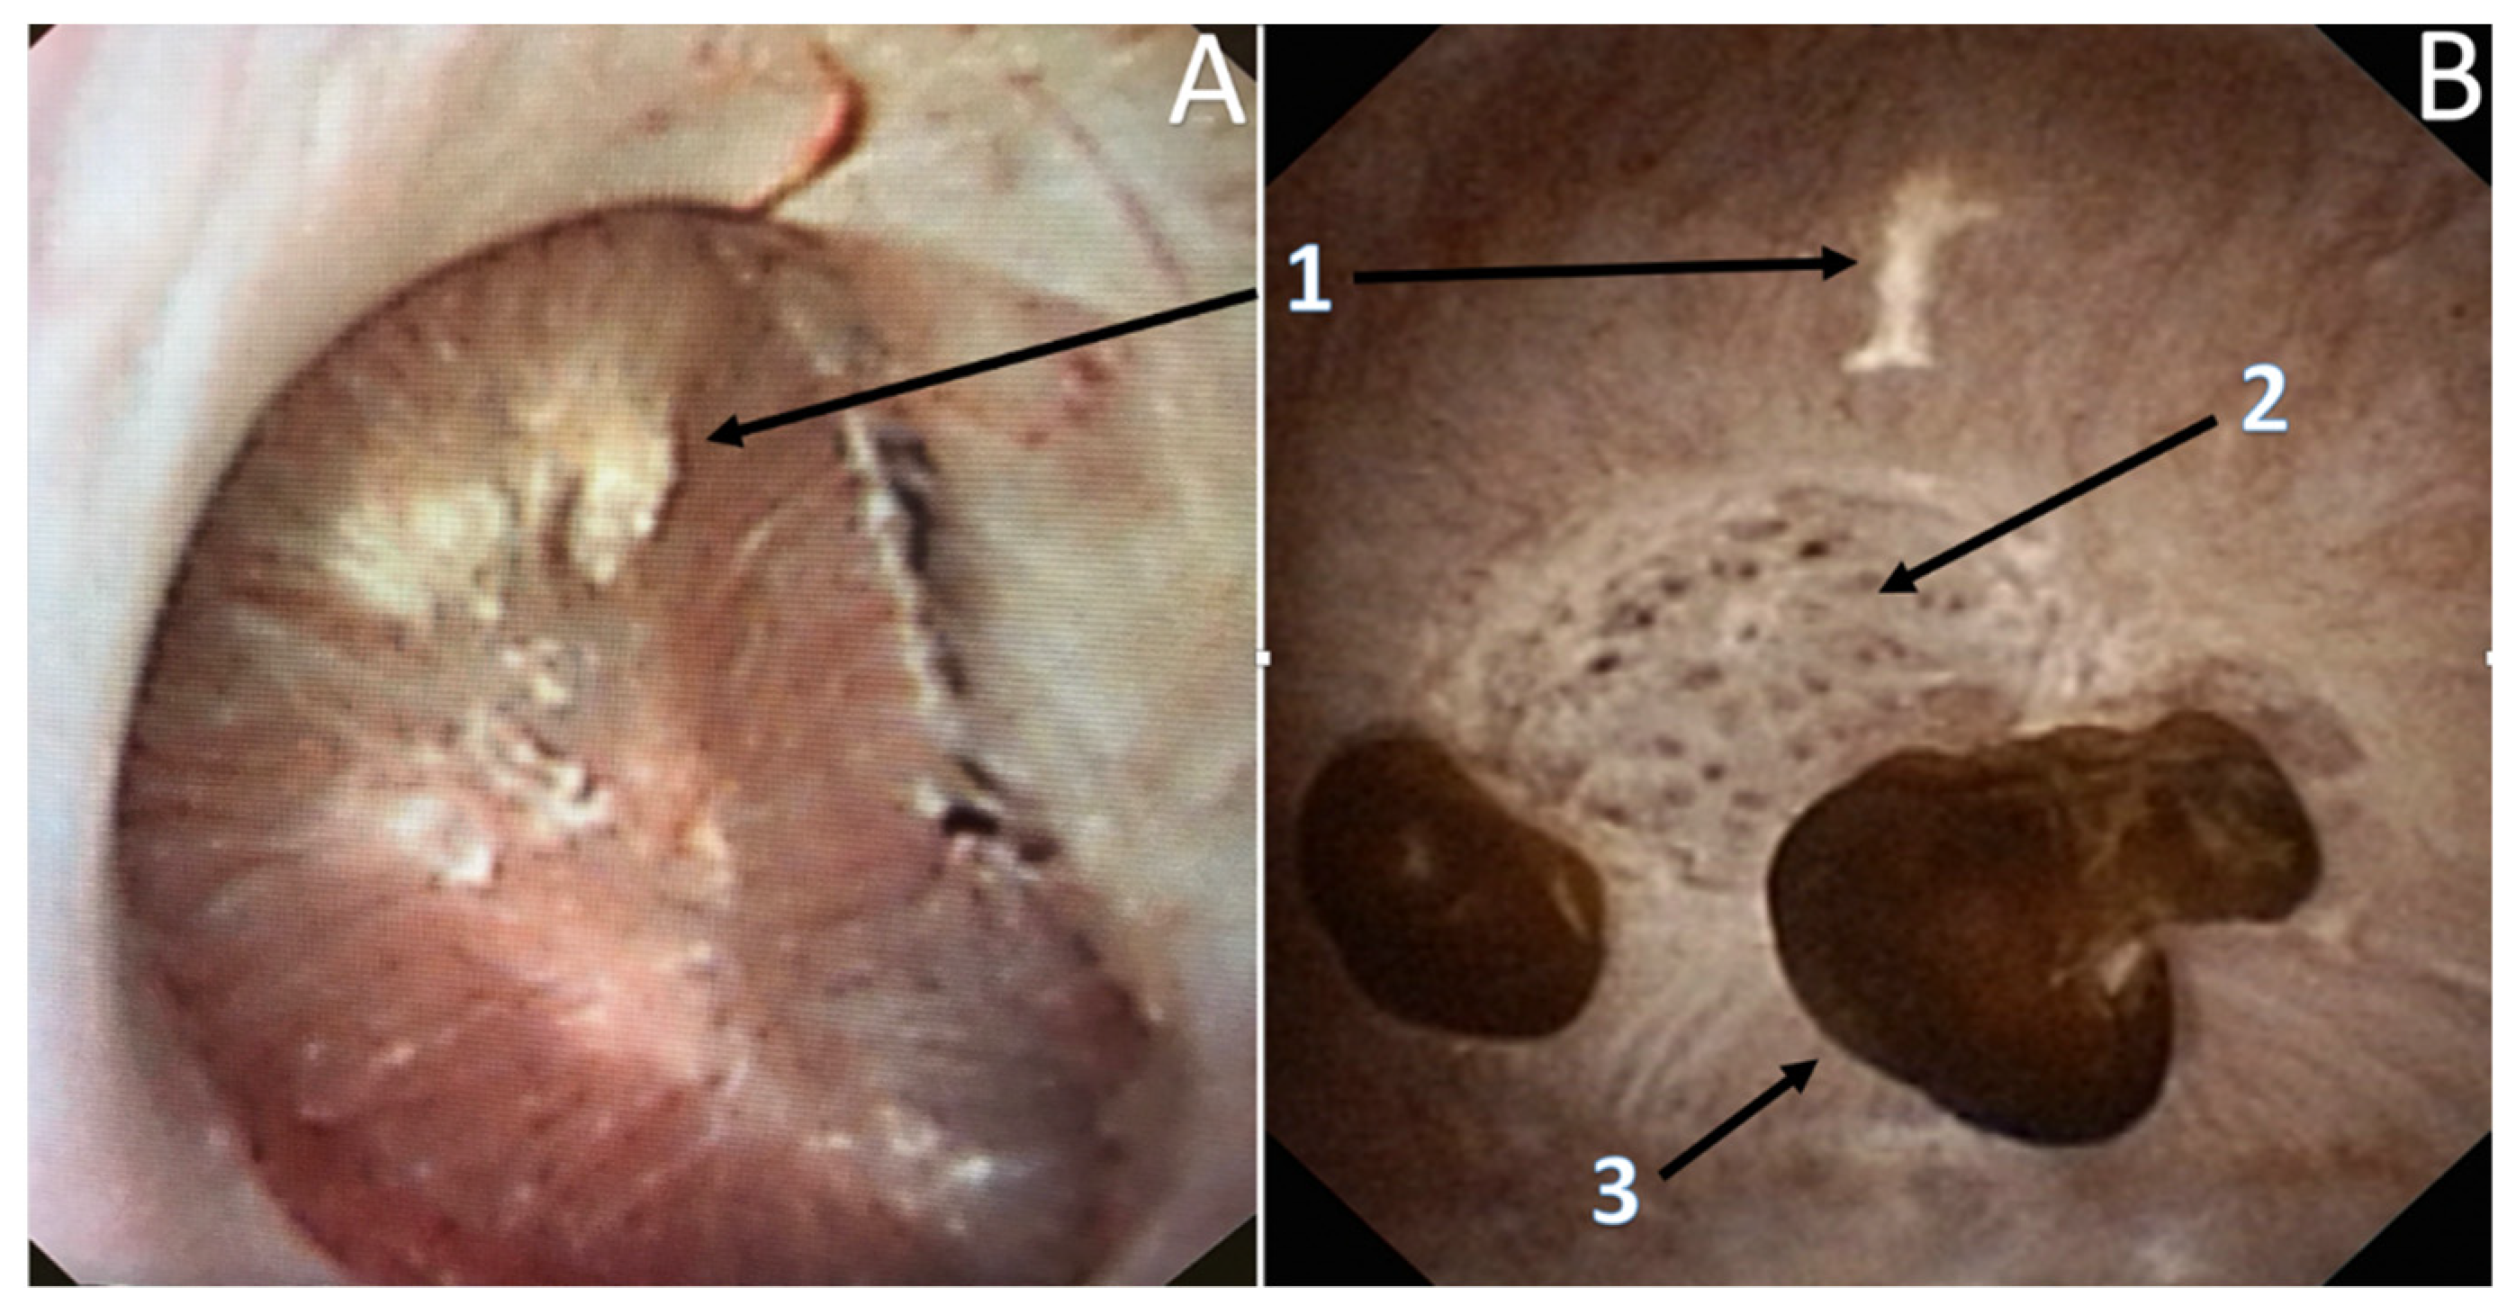

3.3. Endoscopic Papillary Recognition (EPR)

3.4. Endoscopic Stone Recognition